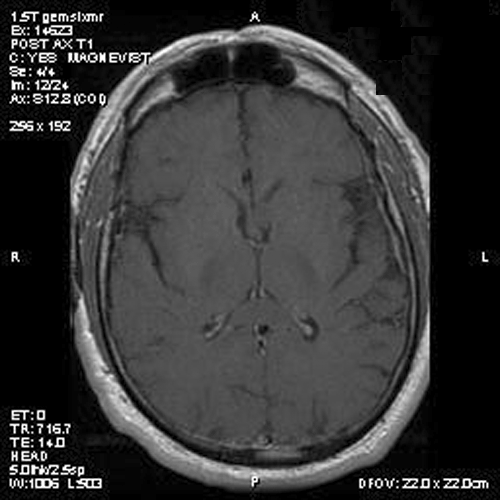

Image of the case: In the left frontal horn there is a well demarcated, subependymal mass measuring approximately 1.1 x 0.5 cm which is relatively hyperintense to white matter on T1-weighted image (Panel A and B) as well as T2-weighted image (Panel C) sequences. It does not enhance on the post contrast images. There is no obstruction of the foramen of Monro.

There is no endothelial proliferation or necrosis. An  intraoperative diagnosis of glial neoplasm was made. The lesion was entirely resected. On paraffin section, the lesion has a hypocellular background decorated by many small microcysts, often in clusters, that contain mucoid material and small cluster of nuclei that resemble bundles of flowers (Panel I and J).  The nuclei are bland. There was no mitosis, endothelial proliferation or necrosis (Panel K and L).